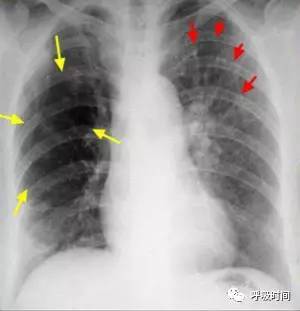

图 8 肺渗出性病变影(蓝箭头)并胸腔积液(红箭头)——病毒性肺炎